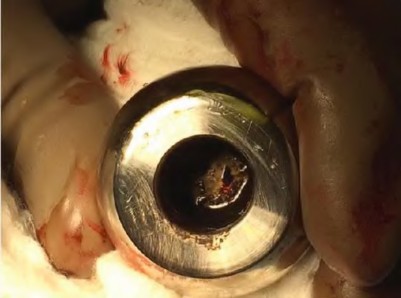

Which of the following histological findings is pathognomonic for an Aseptic Lymphocyte-Dominated Vasculitis-Associated Lesion (ALVAL) in the setting of a failed metal-on-metal THA?

A 60-year-old male presents with groin pain 8 years after a metal-on-metal total hip arthroplasty. Lab results show elevated serum cobalt and chromium levels. MRI with MARS (Metal Artifact Reduction Sequence) shows a solid and cystic mass communicating with the joint space. What is the characteristic histological finding in the periprosthetic tissue of this condition?